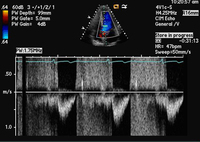

Pulsed wave Doppler of the regurgitant jet

From the collections of Dr Sanjeev Wasson and Dr Nishant Kalra; used with permission